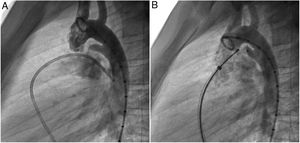

A coil was used in 139 patients (62.9%) and an Amplatzer duct occluder was used in 79 patients (35.7%). In the three remaining patients (1.4%), an Amplatzer vascular plug was used for closure (Figures 2-8). Despite the higher overall rate of coil device implantation, Amplatzer duct occluder usage had been clearly superior since 2011. Of all coil devices used, 55% were either 4x4 mm or 5x4 mm in size (Figure 9), and of all duct occluder devices used, 72% were Amplatzer duct occluder I 6x4 mm or 8x6 mm in size (Figure 10), which correlates to the fact that most patients who were referred had small- to moderate-sized ductus arteriosus. While ADO II and ADO II AS devices can be implanted in a retrograde fashion, only on two occasions was a retrograde deployment performed (both ADO II devices).

Both patients with history of previous PDA closure were successfully treated. The first was a seven year-old child who had a coil implanted at age three. The procedure was technically difficult, requiring a guidewire capture using a snare catheter to go through the residual PDA (Figure 11), and an Amplatzer duct occluder II 3x4 mm device was implanted successfully. The second patient was a 19 month-old child with PDA and pulmonary hypertension after an unsuccessful surgical ligation. In this case, sizing with a Tyshak balloon was required before implanting an Amplatzer duct occluder II 3x4 mm device (Figure 12).